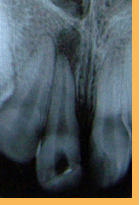

Sequência de radiografias periapicais:

1° quadro - Incisivo central superior apresentando sinais e sintomas de necessidade de tratamento endodôntico;

2° quadro - Instrumento endodôntico tipo lima dentro do canal radicular;

3° quadro - Tratamento endodôntico finalizado com material obturador selando todo o comprimento do canal radicular;